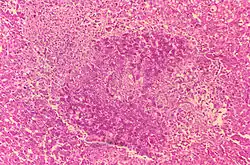

Inkubacja trwa od 14 dni do pół roku. Po tym okresie u samic występują poronienia. Wody płodowe są mętne o brunatnoczekoladowej barwie. Błony płodowe pokryte wybroczynami, zgrubiałe. Kosmki wykazują ogniska martwicowe. Ogniska martwicowe występują także w macicy. U buhajów jądra powiększone są z ogniskami martwiczymi i rozrostem łącznotkankowym.